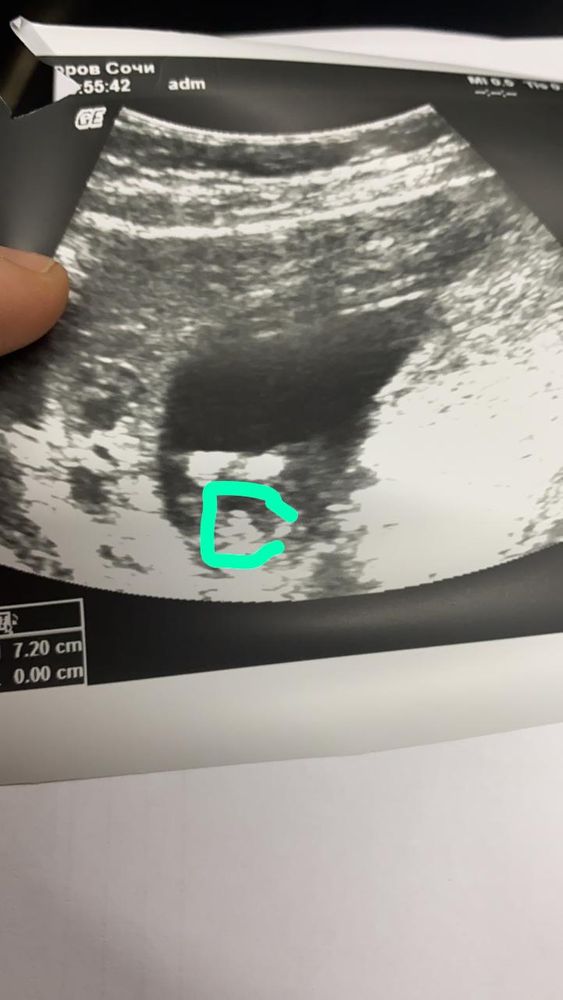

в 13 недель уже увидели писюн, не бугорок 😁 сомнений не осталось

Туда или обратно, значит у моего тоже писюн увидели...